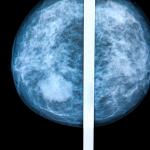

Mammography remains the standard means of screening for breast cancer. For women with denser breast tissue, the superimposition of tissue may mask early tumors even for the most observant of radiologists.

mammography